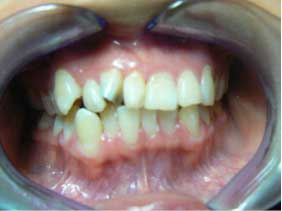

She came to me for an orthodontic consultation. She was 24 years old and hoping to marry her then-boyfriend at some point, but she didn't like her smile; she felt it was unattractive. So we gathered her orthodontic records and pointed out to her that it appeared she had either a supernumerary tooth or over-retained primary tooth between her upper centrals. Along with this, she also had some minor crowding on her lower teeth. She had a Class I molar relationship that I hoped to maintain.

This is a case that I took on early in my career as a wannabe orthodontist.